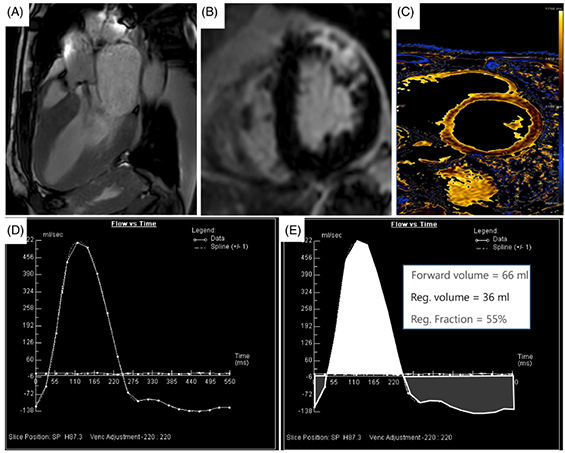

L'IRM est plus performante et reproductible que l'échocardiographie (10). L'évaluation de la fuite aortique ne nécessite pas d'injection de gadolinium et consiste en une mesure directe du volume régurgité en utilisant une cartographie des vitesses juste au-dessus de la valve aortique (imagerie en contraste de phase 2D) dans un plan perpendiculaire à la direction du flux sanguin. Une fois le plan de coupe obtenu, l'opérateur place une zone d'intérêt arrondie sur l'aorte et un post-traitement dédié analyse le flux sanguin à travers le plan aortique en générant une courbe de flux, qui permet de calculer le volume aortique antérograde (volume d'éjection systolique aortique), le volume régurgitant aortique et la fraction de régurgitation (volume régurgité/volume antérograde) (Figure 3).

Figure 3.

A : Plan de coupe juste au-dessus de la valve.

B : Séquence en contraste de phase, le cercle rouge représente la zone d'intérêt tracée par l'opérateur.

C : Courbe de flux à travers le plan aortique. Tout ce qui est sous la ligne bleue représente la fuite aortique.

D : Quantification IRM de la fuite aortique avec un volume antérograde à 157ml, un volume rétrograde à 82 ml et une fraction de régurgitation à 82/157=52 %.

Figure 4. IRM d'une insuffisance aortique en vue 3 cavités (A), présence de rehaussement tardif au niveau de la paroi antérieure et antéro-latérale du ventricule gauche témoin de fibrose localisée (B), T1 mapping permettant l'évaluation de la fibrose diffuse (C) et courbes des flux antérogrades et rétrogrades au niveau de la valve aortique.